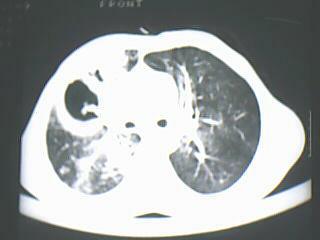

以下是引用随光逐影在2009-8-7 15:40:00的发言:[br]考虑右肺继发性肺结核并右肺上叶空洞形成,两肺支气管播散;不排除右肺上叶空洞内霉菌感染可能。

以下是引用jiangjing在2009-8-7 14:38:00的发言:[br]右上肺张力空洞,酐珞坏死灶,支气管扩张,多发播散灶,纵膈淋巴结显示,胸膜增厚---结核